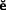

Fig. 12-35 The Merritt EZ Cast Post system. A, The canal is lubricated and excess lubricant removed with paper points. The post was previously trimmed until its beveled portion protruded about 1.5 to 2 mm above the tooth preparation. B, A stick of the thermoplastic material is heated. C, The plastic rod is covered for about two thirds of the anticipated post length. D, The coated post is inserted and can be removed in 5 to 10 seconds. E, After any protrusions have been removed, the core is built from autopolymerizing resin and trimmed to ideal tooth preparation form. F, The completed custom post and core.

(From Rosenstiel SF, et al: Custom-cast post fabrication with a thermoplastic material. J Prosthet Dent 77:209, 1997.)